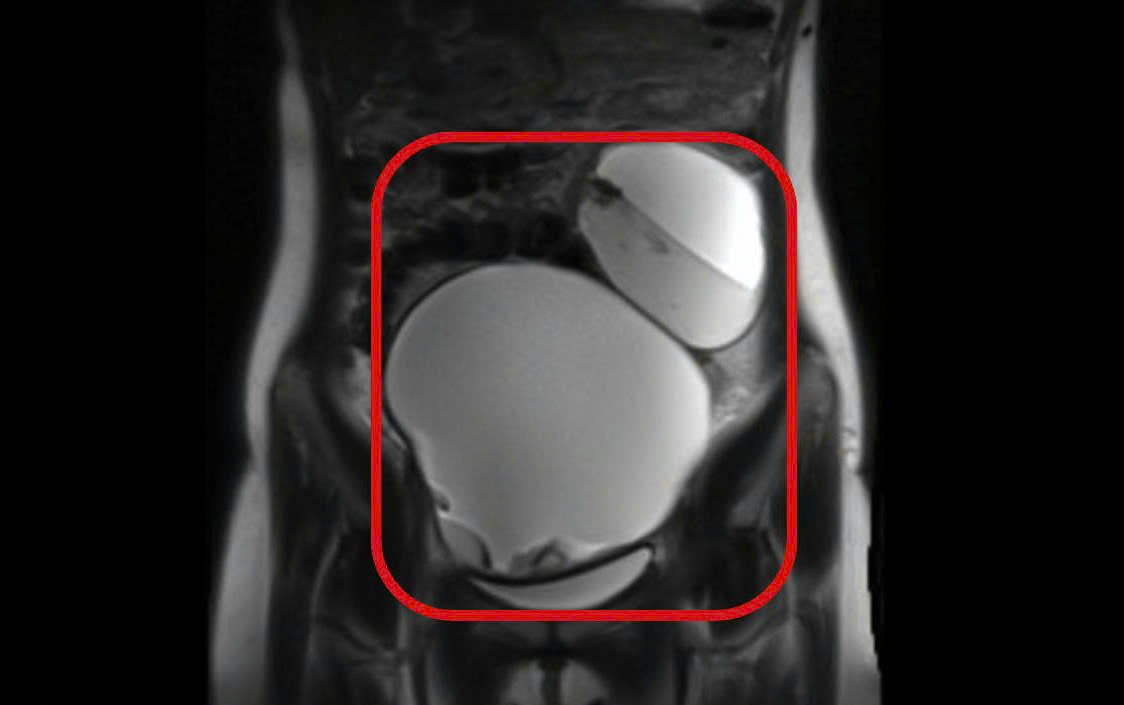

Hai buồng trứng bệnh nhân đều có khối u với kích thước lớn. Ảnh: B.S

Bệnh nhân nhập viện ngày 19/12, trong tình trạng đau bụng hạ vị dữ dội, chưa ghi nhận tiền sử bệnh lý phụ khoa. Qua thăm khám lâm sàng và chụp MRI, các bác sĩ ghi nhận tử cung không bất thường, tuy nhiên cả 2 buồng trứng đều có khối u choán chỗ.

Cụ thể, khối u buồng trứng phải có kích thước khoảng 13×15cm, khối u buồng trứng trái khoảng 8×10cm, bên trong chứa dịch, mỡ và vôi hóa, ranh giới rõ. Đáng chú ý, cả hai khối u đều bị xoắn, đây là biến chứng cấp cứu nguy hiểm. Bệnh nhân được chẩn đoán u bì buồng trứng 2 bên xoắn và được chỉ định phẫu thuật khẩn trương.